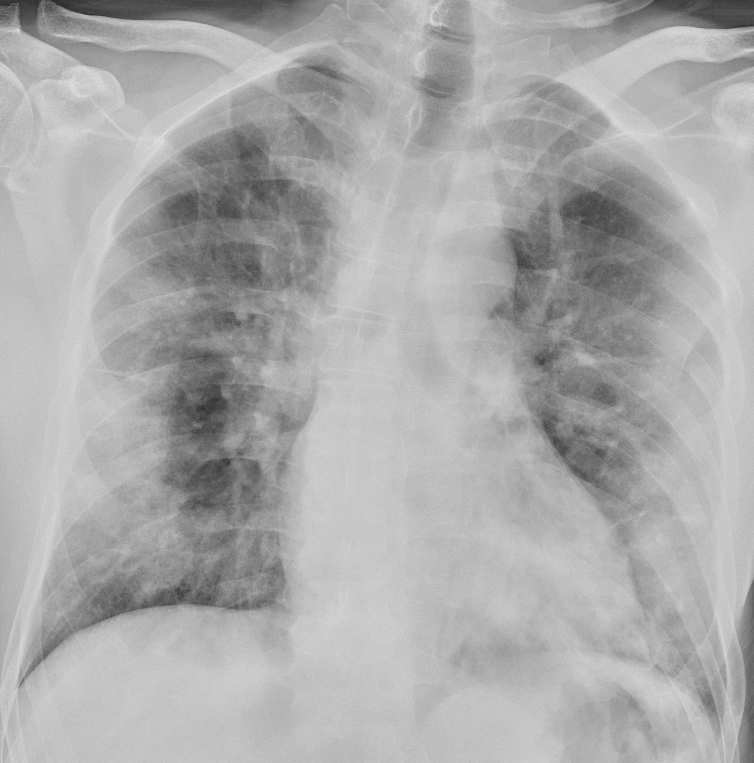

I et materiale fra Hongkong hadde 69 % funn på røntgen thorax før behandling (baseline), men 9 % hadde funn på røntgen thorax før positiv PCR (14). Sensitiviteten for røntgen thorax var 69 % og for PCR 91 %. Vanligste røntgenfunn var bilateral konsolidering og mattglassfortetninger med perifer og kaudal distribusjon. Forandringene var mest uttalt 10–12 dager etter symptomdebut. Figur 1 og figur 2 viser typiske funn på røntgen thorax ved covid-19.

Typiske CT-funn varierer med symptomvarighet og kan deles i tre stadier: en tidlig fase, en intermediær fase som strekker seg fra 3–5 dager etter symptomdebut, og en senfase. Det er ikke alltid funn på CT de første dagene etter symptomdebut. I et materiale med symptomatiske, men uspesifiserte pasienter hadde 56 % normale funn på CT innen to dager etter symptomdebut (12), avtakende til 9 % 3–5 dager etter symptomdebut og 4 % 6–12 dager etter symptomdebut. Funnhyppighet varierer med sykdommens alvorlighetsgrad. Ved første gangs bildediagnostikk var det normale funn hos 18 % i en gruppe pasienter med ikke alvorlig sykdom, men hos bare 3 % av pasienter med alvorlig sykdom (15). Typiske CT-funn er multiple, bilaterale mattglassfortetninger med perifer distribusjon, hyppigst lokalisert i underlappene. I intermediær fase er det økende innslag av konsolidering (tette infiltrater) og affeksjon av flere lapper samt økt septering med brosteinsmønster (crazy paving) som tegn på interstitiell affeksjon. I senfasen er det økende total utbredelse, men mattglassfortetninger og konsolidering er fremdeles dominerende funn (12, 16). Figur 4, figur 5 og figur 6 viser typiske funn på CT i ulike faser av covid-19.

Ved alvorlig sykdomsforløp kan det påvises distorsjon av lungearkitekturen, traksjonsbronkiektasier, forstørrede lymfeknuter og pleuravæske. Dette er funn som ikke er spesifikke for covid-19 (17).